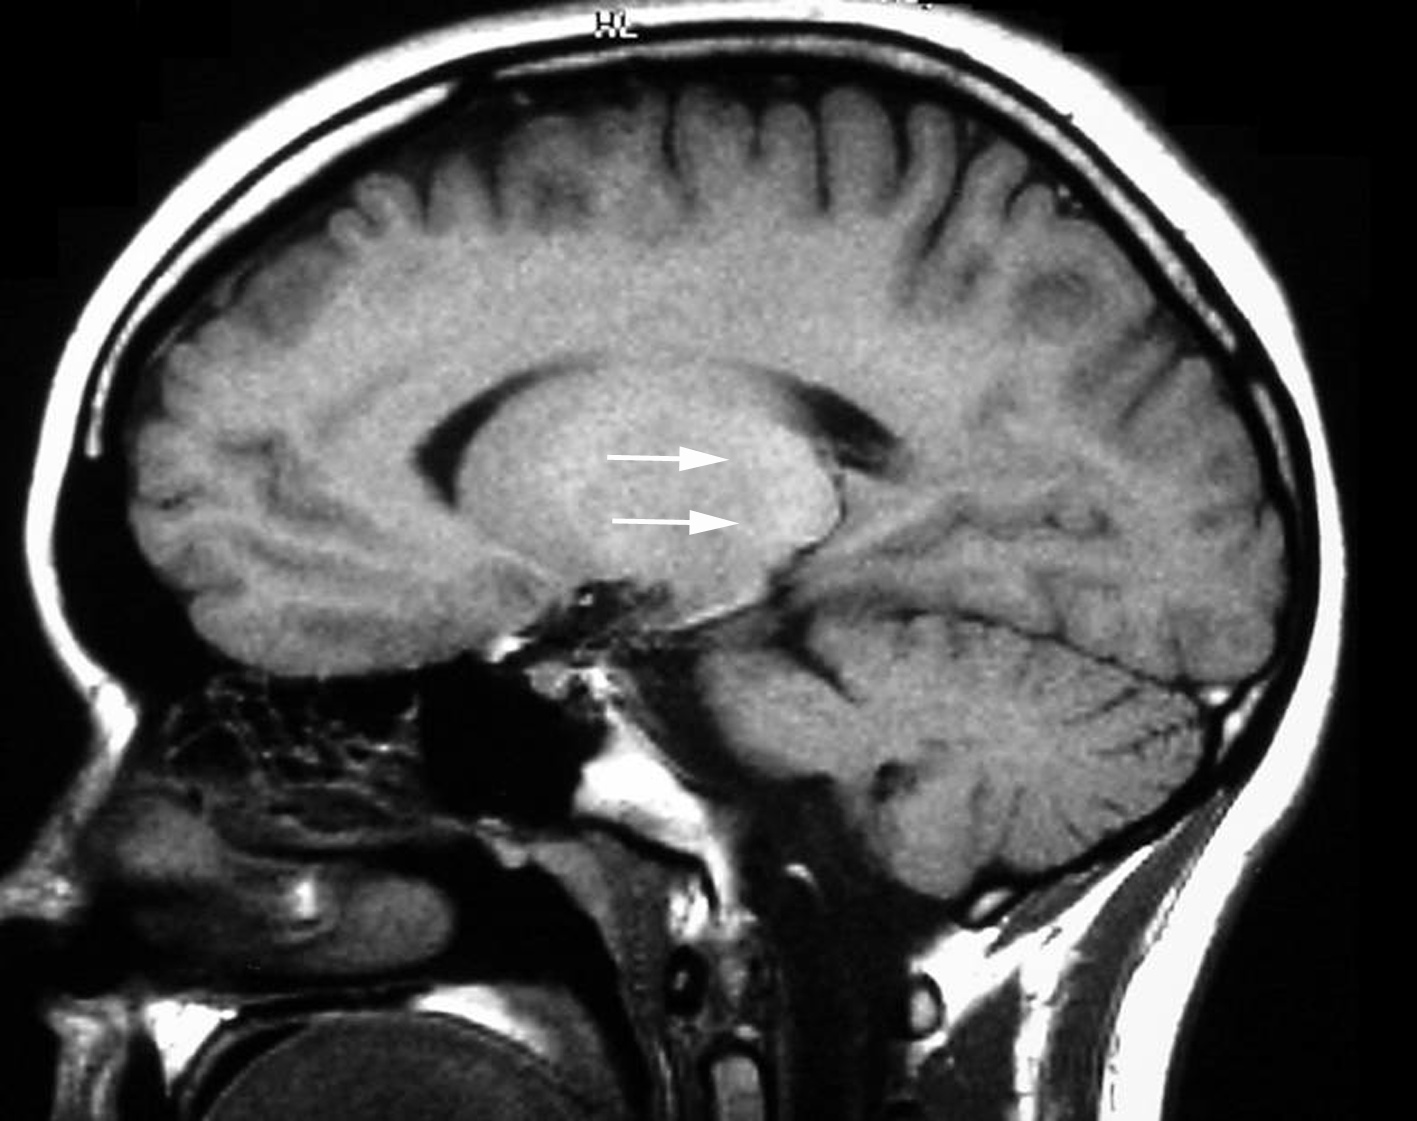

2. vCJD T1

vCJD T1